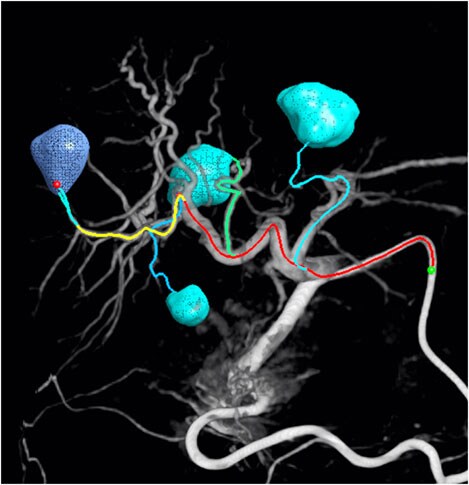

EmboGuide: treatment planning and Live Image Guidance for embolization

The segmented lesions are verified based on the planned position of the catheter tip. During the procedure, Live Image Guidance assists clinicians in reaching each of the verified feeders for a selective or even super-selective embolization.

Dr. Miyayama, Department Head of Diagnostic Radiology, Fukui-ken Saiseikai Hospital, Japan, says: “Trans-arterial chemo-embolization (TACE) is not considered a curative treatment, but with advances and an ultra-selective approach, it can in some cases come close. The physician's burden can be considerably mitigated by use of EmboGuide.” EmboGuide’s feeder detection step helps the clinician to detect even small hepatocellular carcinomas and their feeding branches.